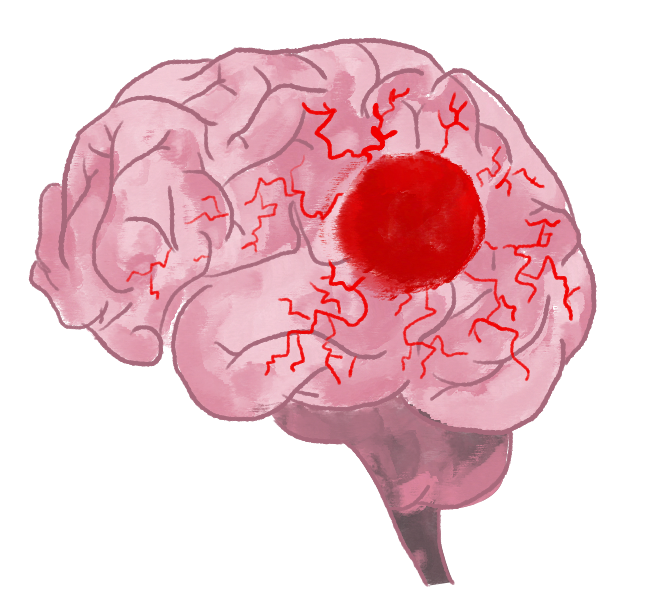

Una aproximación a la migraña

«La migraña supone una disfunción del sistema de dolor, que es una red muy compleja que interviene en muchos núcleos dentro del cerebro. Cuando esa red se activa, da lugar a una serie de procesos, y entre ellos, hay una inflamación en las meninges. Se origina lo que llamamos una meningitis aséptica, porque es no infecciosa, y se produce una inflamación alrededor de los vasos que están en las propias meninges. Y por eso, por ejemplo, la pulsación del vaso sanguíneo, que es normal, se percibe. Esa es la razón por la que el dolor de la migraña es un dolor pulsátil, que se incrementa con el movimiento de la cabeza, o que hace que de forma instintiva el paciente bloquee el cuello», explica la doctora Margarita Sánchez del Río, neuróloga referencia internacional en el campo de las migrañas y cefaleas, que actualmente trabaja en la sede madrileña de la Clínica Universidad de Navarra.